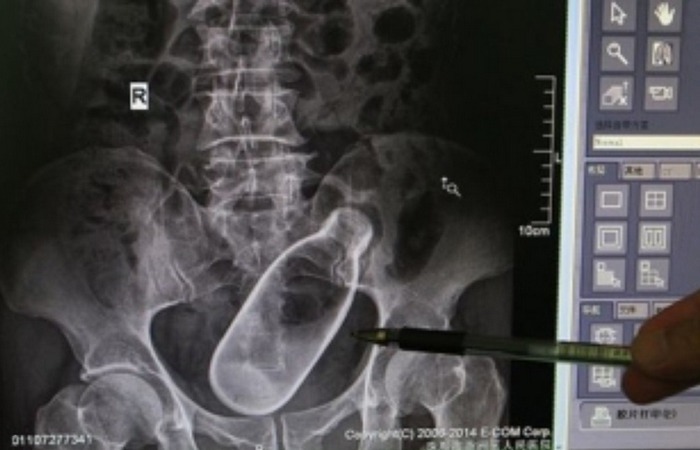

У Вас тут в прямой кишке живые рыбы шалят…

Алкоголь человеку точно не друг, а как раз наоборот. В состоянии алкогольного опьянения 45-летний китаец зачем-то засунул в собственный анус двух живых рыб-вьюнов. Это выяснилось, когда его привезли в больницу с высокой температурой, низким артериальным давлением и сильной боли в желудке. Мужчина признался врачам, что он сделал, и оказалось, что один из вьюнов забрался к нему в желудок, а второй – прорвал стенку кишечника. Медикам пришлось провести абдоминальную цифровую рентгенографию, чтобы найти рыб внутри несчастного, но всё закончилось хорошо.